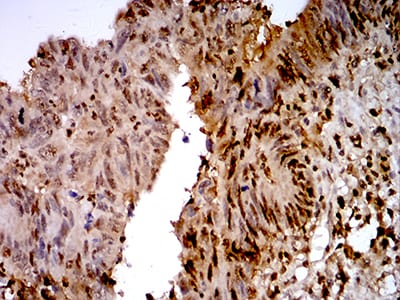

IHC 1/200 - 1/1000 Human,Mouse,Rat

TTF1 (Thyroid Transcription Factor 1), also known as NKX2-1. is a transcription factor encoded by the NKX2-1 gene located on chromosome 2p13. It belongs to the NKX2 family of homeodomain-containing proteins and plays a critical role in embryonic development, particularly in the morphogenesis and differentiation of the thyroid, lung, and specific regions of the brain. In diagnostic pathology, TTF1 is widely utilized as an immunohistochemical (IHC) marker to determine the origin of tumors. It is highly expressed in adenocarcinomas of the lung (specifically terminal respiratory unit-type) and thyroid neoplasms (e.g., papillary and follicular carcinomas). TTF1 positivity helps distinguish primary lung adenocarcinomas from squamous cell carcinomas (usually TTF1-negative) and metastatic tumors from other sites. Additionally, it is expressed in a subset of neuroendocrine tumors, including small cell lung carcinoma. However, TTF1 expression can vary depending on tumor type, differentiation status, and antibody clones used (e.g., SPT24 vs. 8G7G3/1 clones). Its specificity and sensitivity make it a cornerstone in tumor classification, though results should always be interpreted alongside clinical, radiographic, and histologic findings.